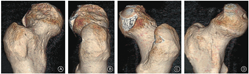

男,28岁,快递员。因骑电动车撞击花坛致伤2 h入院。急诊体格检查:右髋部疼痛、右下肢外展外旋畸形伴活动受限,远端肢体感觉及循环可。急诊摄骨盆正位X线片示右髋关节前脱位,股骨头塌陷(图1A);即行髋关节脱位手法闭合复位以避免股骨头脱位时间过长影响血供,复位后摄X线片证实右侧髋关节已复位(图1B)。骨盆CT示患者右侧股骨头外前象限压缩(图2);三维重建示股骨头塌陷约2.5 cm×3.0 cm,压缩体积略大于股骨头体积的10%(图3)。

术中见股骨头前上方约2.5 cm×3.0 cm压缩,大小与术前CT测量结果一致;负重关节面软骨缺损,骨质塌陷。先应用骨刀凿除塌陷的骨软骨区,体积约3 cm×3 cm×1.5 cm;于股骨头内下头颈交接区取相同大小的骨软骨块,移植于压缩区域,修剪形状使股骨头关节面光滑;克氏针临时固定,再用直径3.0 mm的全螺纹无头钉埋头固定(常州华森医疗器械股份有限公司,中国)。取同侧3 cm×3 cm×2 cm髂骨外板修剪后植于股骨头内下供区,尽量保持髂骨外板和股骨头交界处光滑,克氏针临时固定后再用两枚3.0 mm全螺纹无头钉埋头固定(图4)。